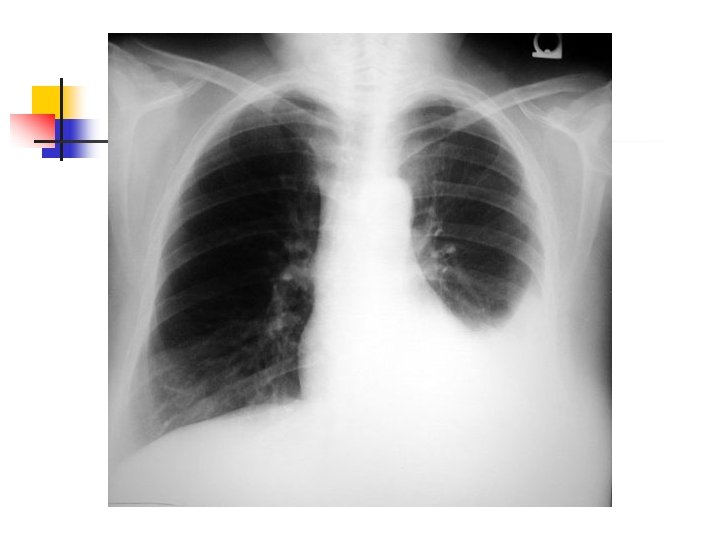

Aproximación diagnóstica: Radiología n n n 250 ml son necesarios para provocar alteraciones radiológicas. Primer signo: Borramiento del SCD Damoisseau. Desviación de estructuras. Derrame tabicado.

Aproximación diagnóstica: Ecografía n n Indicaciones Confirmación de DP en casos no claros Guiar punción en derrames pequeños o tabicados Ha demostrado reducción en la incidencia de Neumotórax (Evidencia C) Porcel JM, Light RW. Diagnostic aproach to pleural effusion in adults. Am Fam Physician 2006: 73: 1211

Aproximación diagnóstica: TAC Siempre TAC contraste n n Evaluar parénquima vecino Evaluación del mediastino. Desplazamiento contralateral Evaluación de DP tabicado Angio. TC Porcel JM, Light RW. Am Fam Physician 2006: 73: 1211